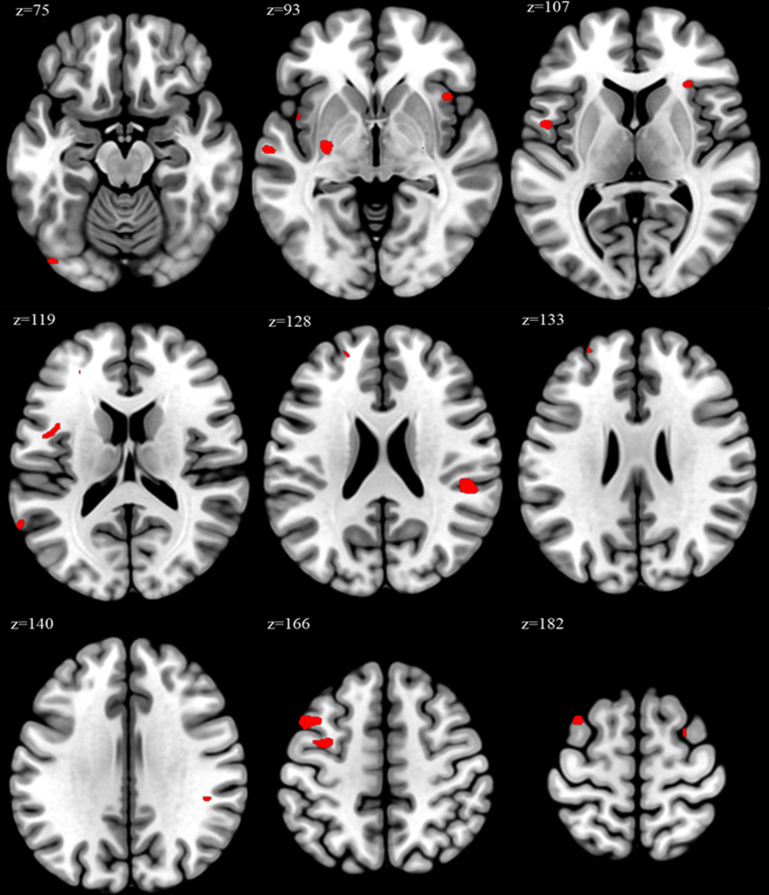

Results: Overworked individuals exhibited significant changes in brain regions associated with executive function and emotional regulation. Atlas-based analysis revealed a 19% increase in left caudal middle frontal gyrus volume in the overworked group compared with the non-overworked group (p=0.006). VBM showed peak increases in 17 regions, including the middle frontal gyrus, insula and superior temporal gyrus (p<0.05). Correlation analyses indicated a positive association between weekly working hours and brain volume changes in the middle frontal gyrus and insula.